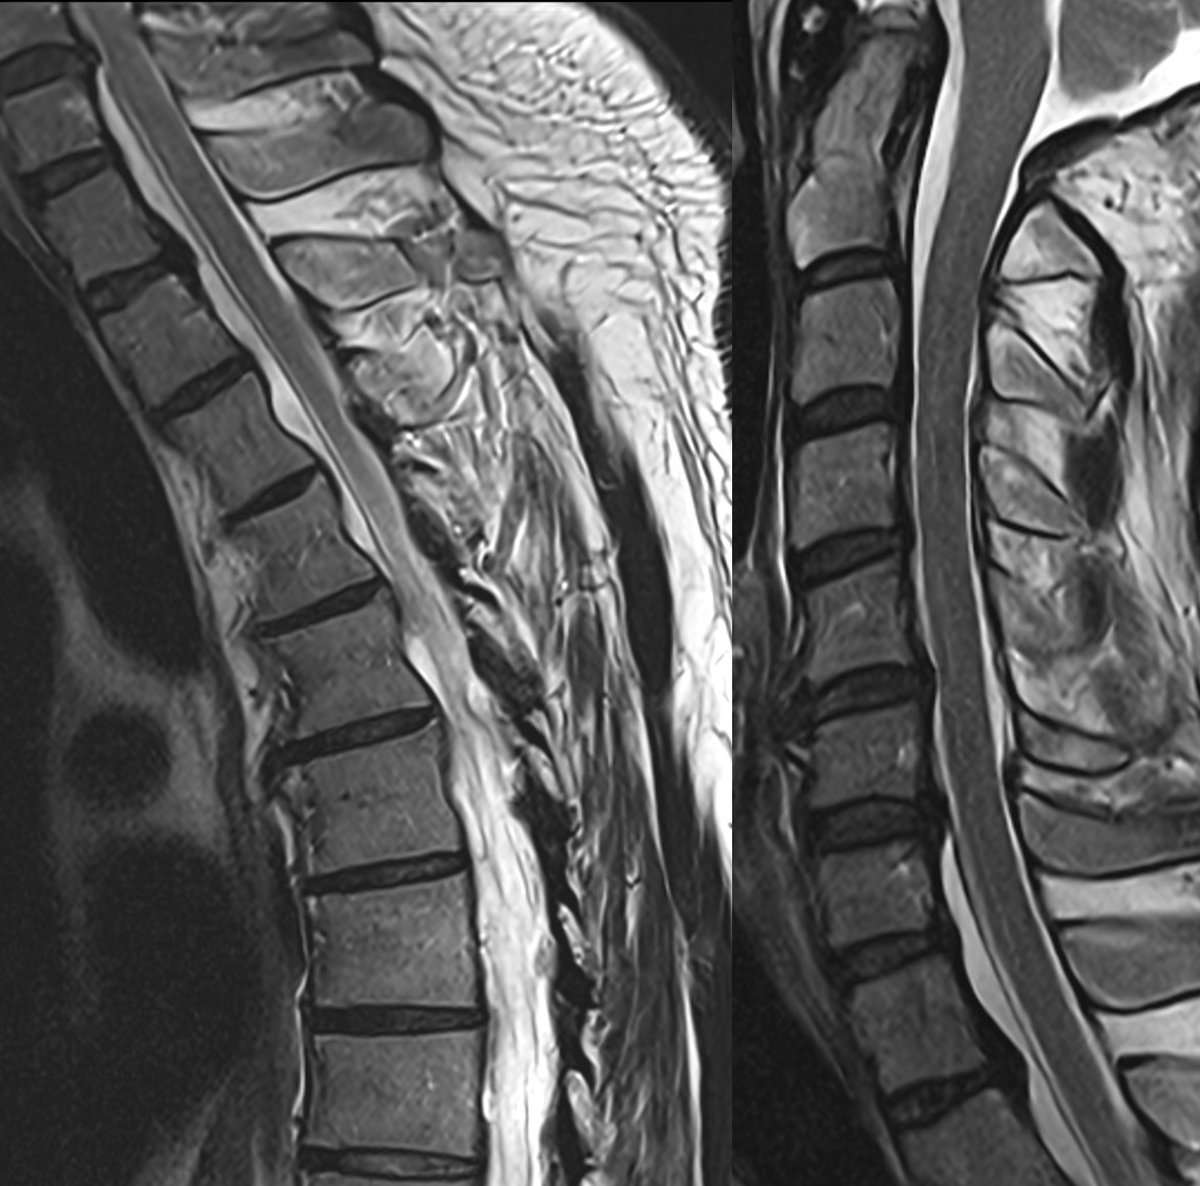

Spinal CSF-venous fistulas almost always arise from meningeal diverticula. The diverticular size can vary from tiny (submillimeter) to massive (think dural ectasia). At least one-third of diverticula change size when a fistula forms @spinalCSFleak pubmed.ncbi.nlm.nih.gov/41730631/